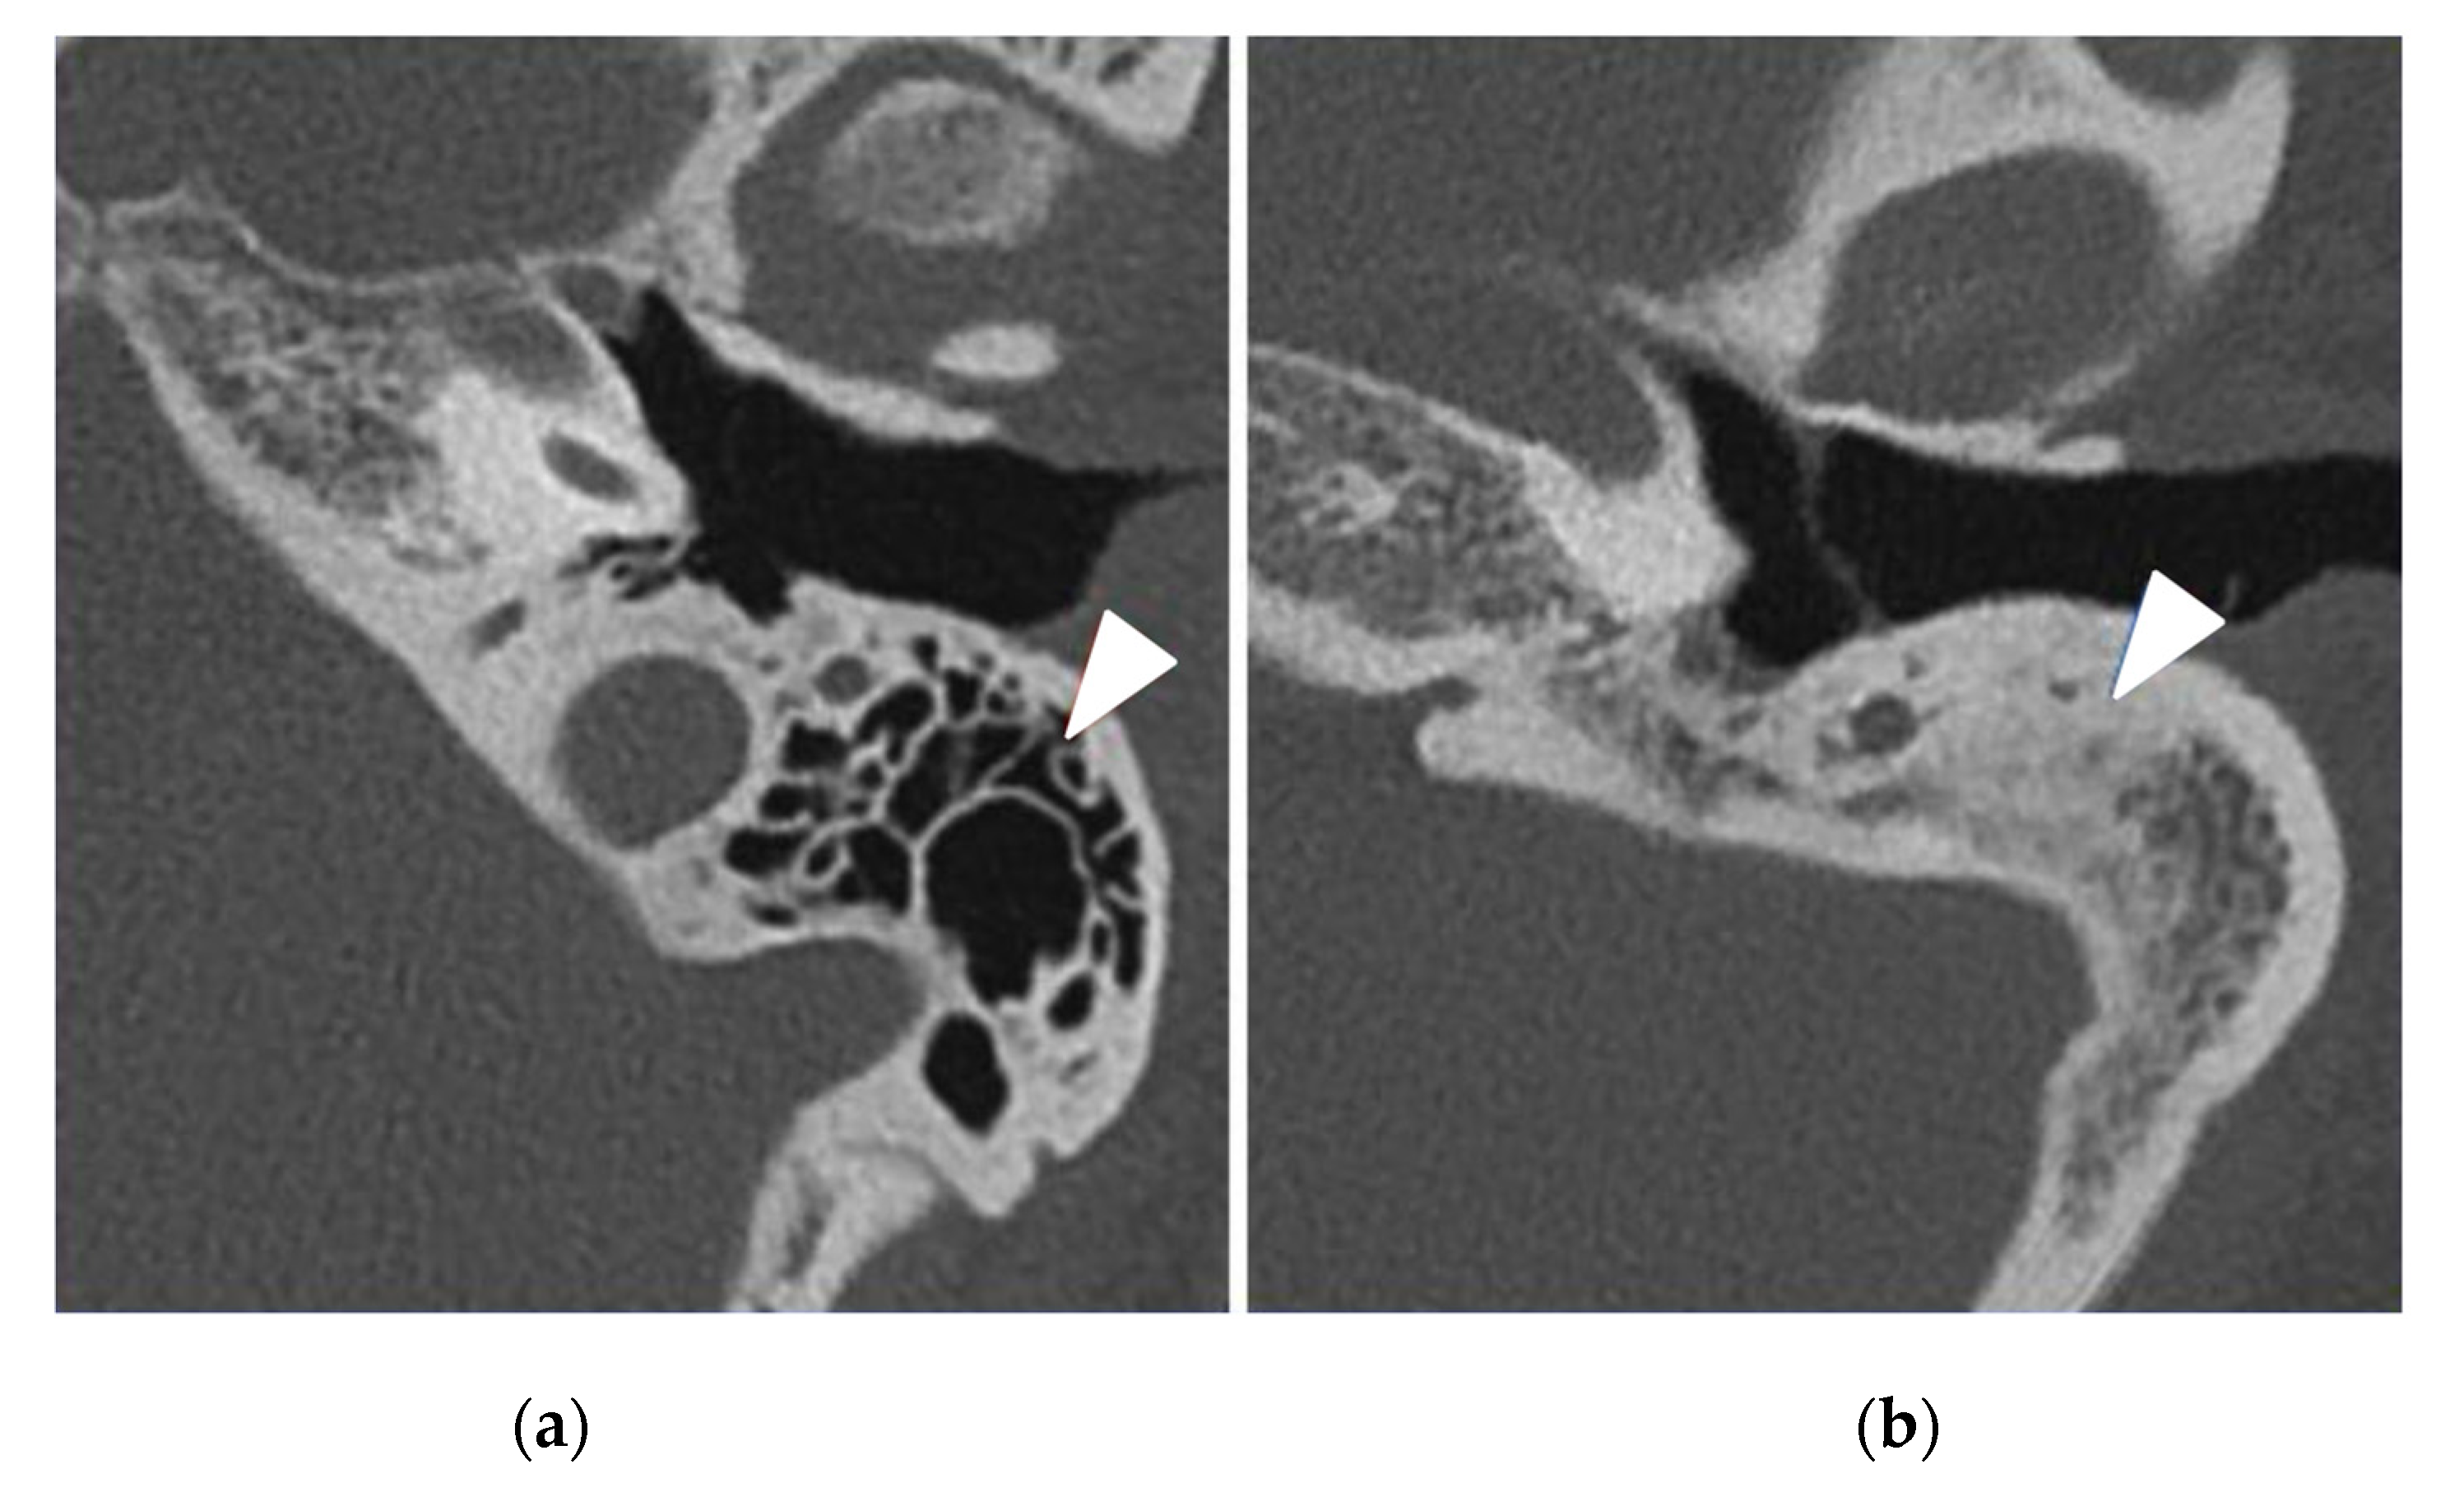

| Abnormal CT scan, | 32 (94%) | 11 (32%) | <0.0001 |

| Mastoid opacification | 13 (38%) | 8 (24%) | 0.19 |

| Mastoid condensation | 21 (62%) | 8 (24%) | 0.01 |

| Middle ear inflammation | 22 (65%) | 7 (21%) | 0.0002 |

| Ossicular anomaly | 12 (35%) | 3 (9%) | 0.01 |